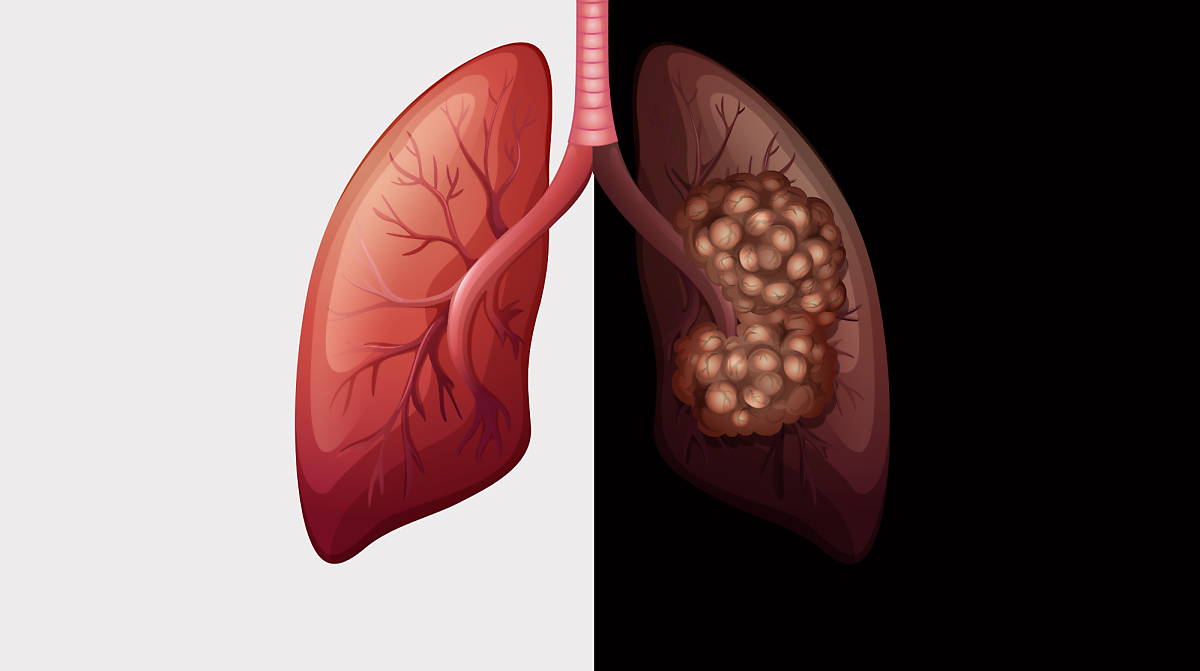

열이 며칠간 지속되거나 해열제를 써도 잘 떨어지지 않는 경우 특히 주의해야 합니다.2. 심한 기침과 누런 가래

폐렴이 생기면 기침이 하루 종일 멈추지 않고,

노란색 또는 녹색 점액 가래가 함께 나오는 경우가 많습니다.

기침 소리가 거칠거나 쌕쌕거리는 경우도 있습니다.

폐렴 증상 3. 호흡 곤란 및 숨 가쁨

계단을 오르거나 평소보다 조금만 움직여도 숨이 찰 수 있습니다.4. 흉통(가슴 통증)

기침하거나 숨을 깊게 쉴 때 가슴, 특히 흉부에 찌르는 듯한 통증이 발생할 수 있습니다.

이는 염증이 **늑막(폐를 감싸는 조직)**까지 퍼졌기 때문이에요.